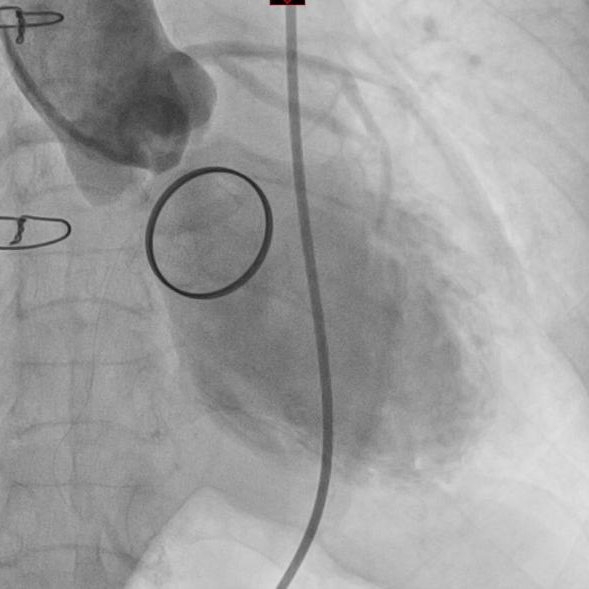

这也标志着重庆康心医院心外科成为大重庆地区为数不多的、掌握多种路径TAVR手术的特色专科之一。